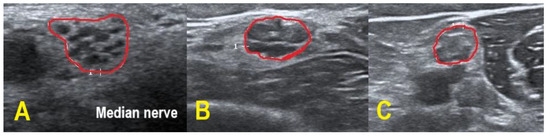

Four CIDP patients and every POEMS syndrome patient showed hypoechoic nerves (class 1), whereas the remaining CIDP patients demonstrated a more heterogeneous pattern with hypo- and hyperechoic fascicles (class 2). No patient exhibited class 3 pattern. In contrast to the patients with CIDP, the examined POEMS syndrome patients featured additional hyperechoic intraneural connective tissue. Figure 3 exemplifies the different HRUS findings.

Therefore, the observed echogenicity patterns in our POEMS patients could be a promising finding. Lucchetta et al. [7] already described hypoechogenic nerves in POEMS syndrome, as was the case in our study. Our POEMS patients presented additional hyperechoic intraneural connective tissue, which is an interesting morphological observation and not known to appear in CIDP. Furthermore, hypoechoic nerves are associated with better treatment response in CIDP (possibly reflecting active inflammation) and can be used as a prognostic marker, while in clinically progressive CIDP, hyperechoic nerves are frequently found (possibly reflecting axonal degeneration [18,21,22]). Follow-up studies have to prove if these findings are applicable to POEMS syndrome patients. The histological correlate behind the increased and hyperechoic interfascicular tissue has to be clarified by histopathological studies in future projects.

Figure 3. HRUS of the right upper arm median nerve. POEMS syndrome patient #1 demonstrated hypoechoic fascicles and hyperechoic intraneural connective tissue ((A) within red border). In CIDP patient #6, HRUS depicted hypoechoic next to hyperechoic fascicles ((B) within red border), whereas HRUS in CIDP patient #9 showed hyperechoic fascicles ((C) within red border).